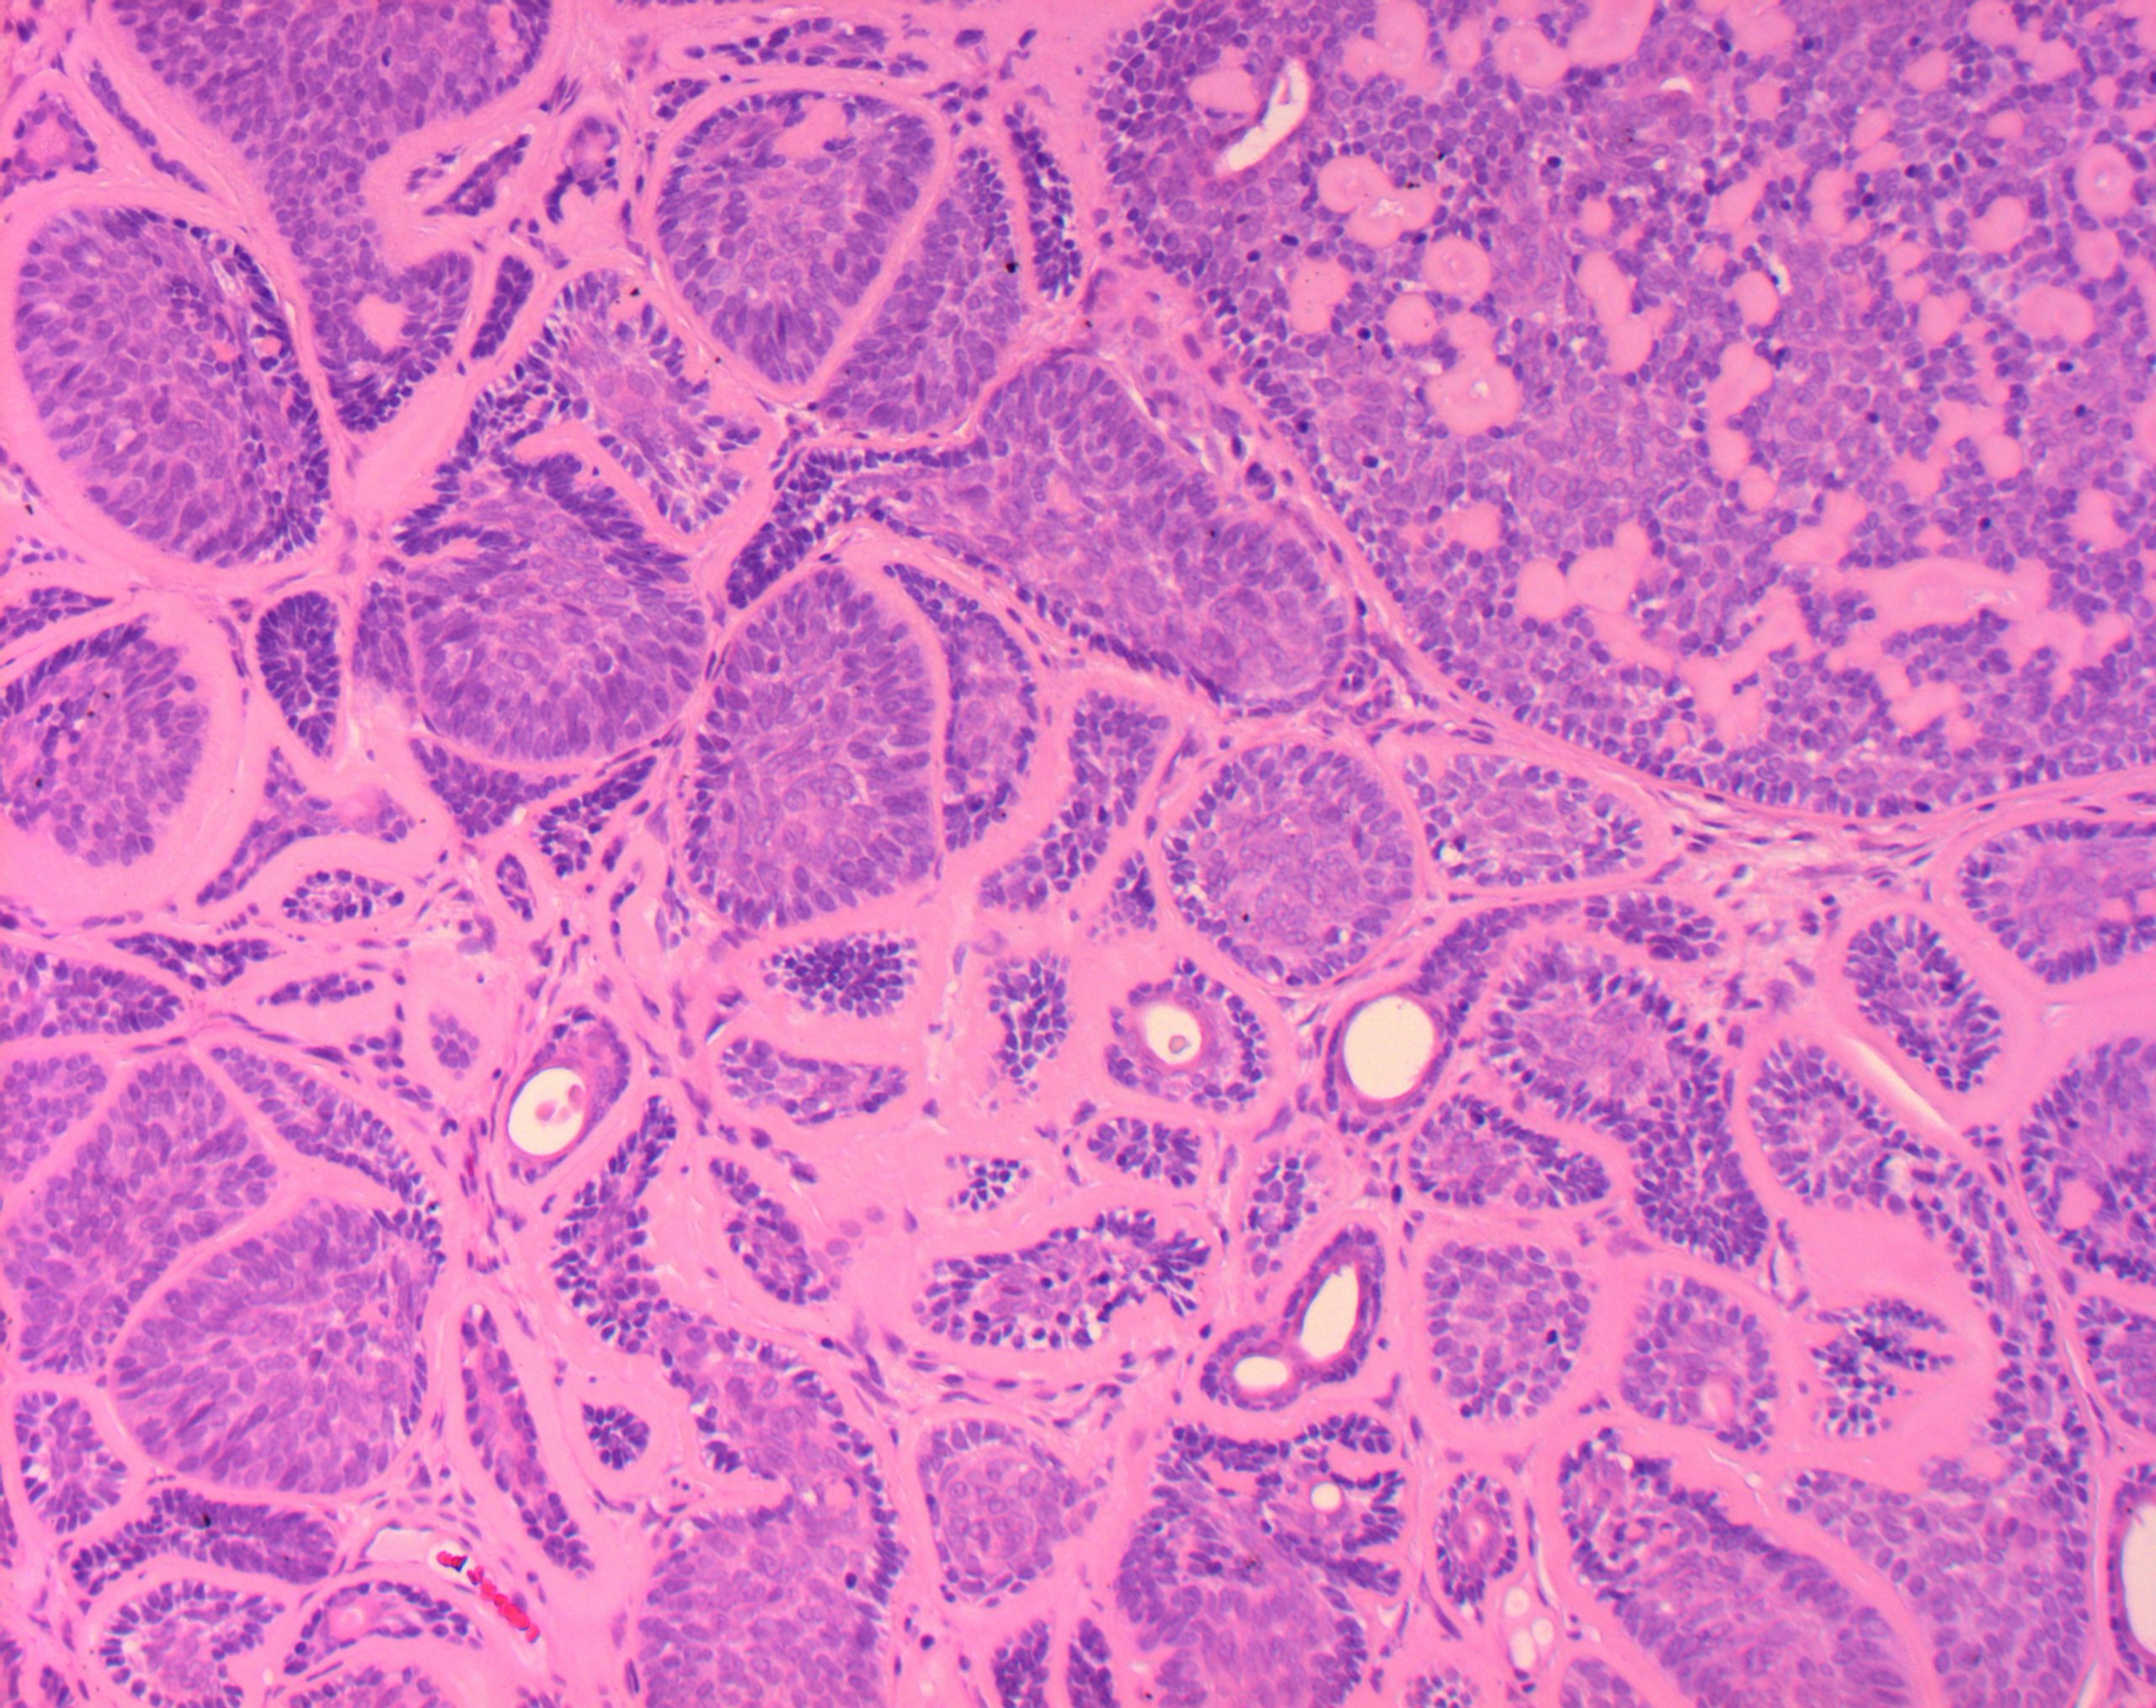

Nous sommes spécialisés dans

Tous les aspects des techniques de laboratoire.